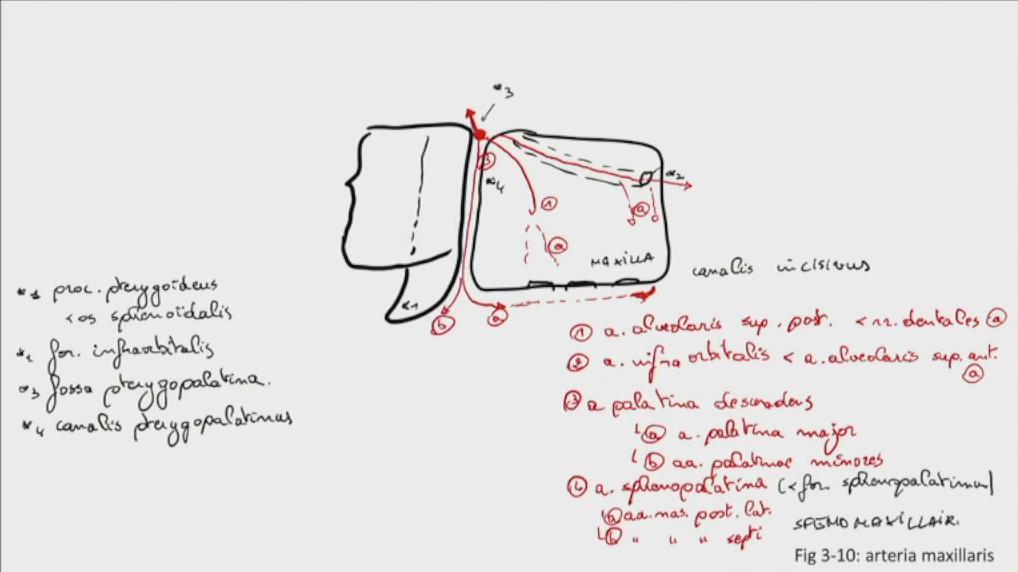

Fig 3.10a: a. maxillaris - sfenomaxillair deel

|

|